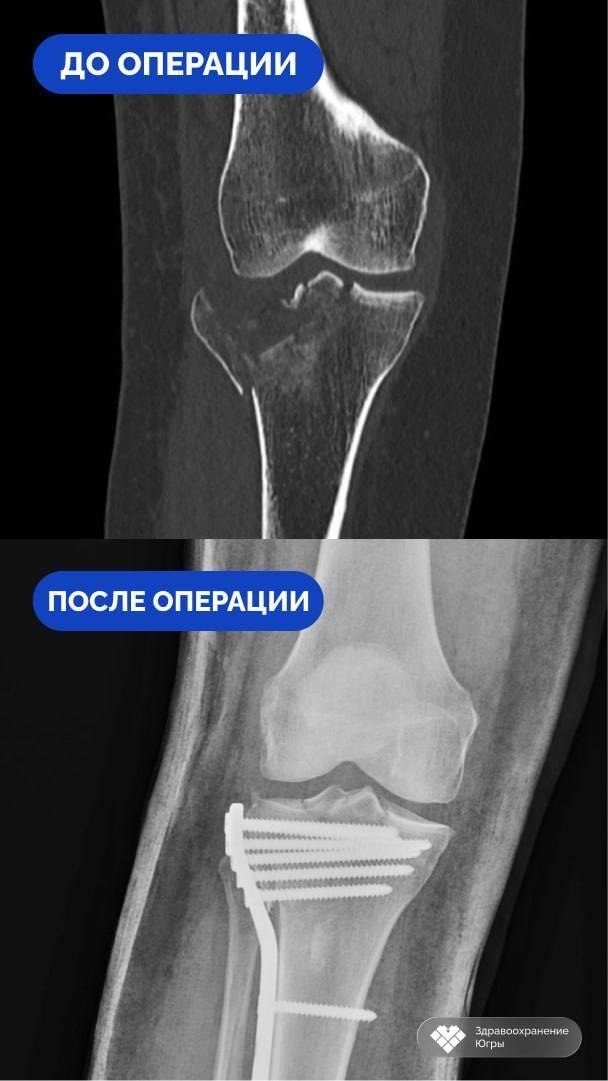

Диагностика выявила оскольчатый импрессионный перелом голени, а также повреждения плечевой и пяточной костей. Лечащий врач Артем Денисенко отметил, что все травмы внутрисуставные, что особенно опасно для нижних конечностей.

Травматологи-ортопеды под руководством заведующего отделением Сергея Глиняного разработали план лечения. Они выбрали методики, которые были эффективны и сохраняли функции суставов. Важным условием для успешного восстановления было максимальное восстановление суставных поверхностей и стабильная фиксация переломов. Операции провели в два этапа.